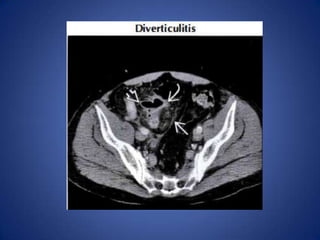

Diverticulitis • Most commoncause in middle-aged and elderly – Can affect patients as young as 25 • Usually long ( 10- 1 5 cm) segment of wall thickening, luminal narrowing, pericolonic infiltration • Extraluminal collections of gas or fluid help confirm diagnosis